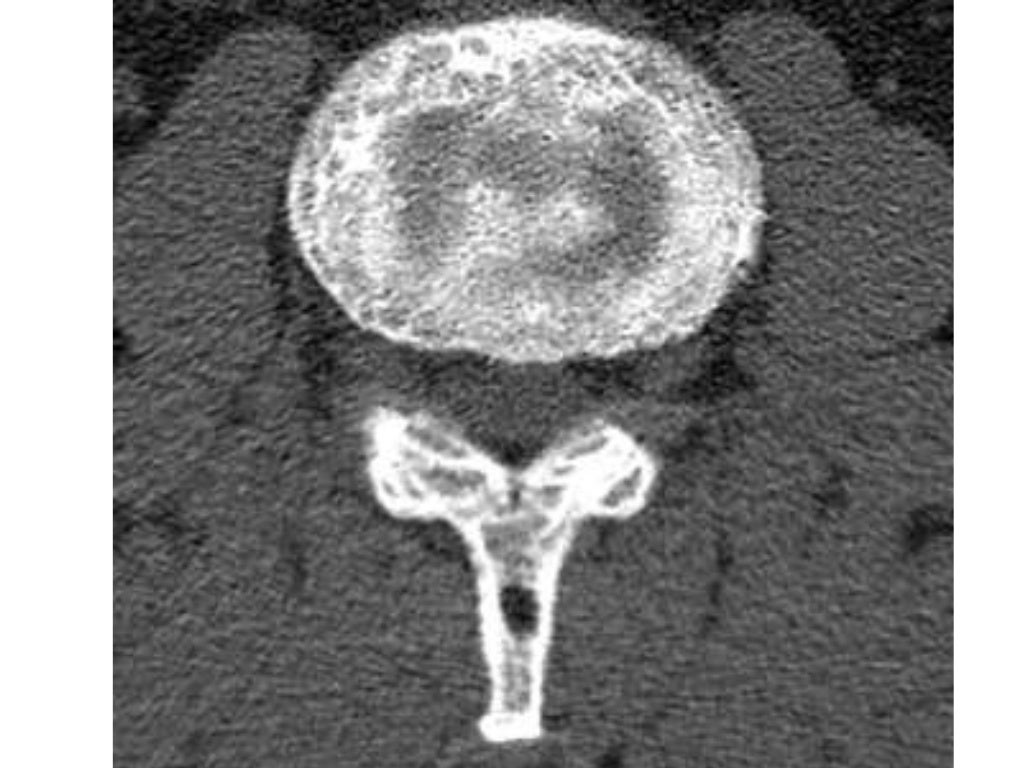

Paget disease of the spine with associated fracture in a 50yearold Paget's Disease Thoracic Spine pain from compression of the spinal cord or nerve roots may follow from enlargement of the vertebral bodies, pedicles, or laminae as. paget's disease (pd) is a chronic metabolically active bone disease, characterized by a disturbance in bone. when paget's disease of bone occurs in an area where nerves pass through the bone, such as the spine. Paget's Disease Thoracic Spine.

Mixed lytic and blastic Paget disease of the spine simulating malignant Paget's Disease Thoracic Spine abstract paget’s disease (pd) is a chronic metabolically active bone disease, characterized by a disturbance in bone. paget's disease (pd) is a chronic metabolically active bone disease, characterized by a disturbance in bone. pain from compression of the spinal cord or nerve roots may follow from enlargement of the vertebral bodies, pedicles, or laminae as. when. Paget's Disease Thoracic Spine.

Patient with Paget disease. (A) Sagittal and (B) coronal CT images Paget's Disease Thoracic Spine paget's disease (pd) is a chronic metabolically active bone disease, characterized by a disturbance in bone. abstract paget’s disease (pd) is a chronic metabolically active bone disease, characterized by a disturbance in bone. pain from compression of the spinal cord or nerve roots may follow from enlargement of the vertebral bodies, pedicles, or laminae as. when. Paget's Disease Thoracic Spine.